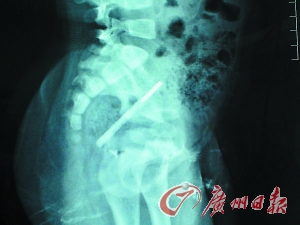

体温计在宝宝肛门内

本报讯(记者涂端玉 通讯员简文杨摄影报道)“医生,麻烦快来看看我们家宝宝,他的体温计断在屁股里取不出来了……”日前,一对年轻的父母抱着一名不到两岁的婴儿焦急万分赶到了中山大学附属第六医院急诊科。专家百般小心才将近10cm的体温计从孩子肛管中取出。专家提醒:婴幼儿光屁股时间长,不止是体温计,异物入肛都机会多多,须提防注意。

幸好,经过手术,医生终于从患儿肛管中成功取出断裂体温计。由于不放心水银在孩子体内是否会造成汞中毒,医生随后还为他抽血进行了肾脏检查,结果显示一切正常。俊俊父母终于松了口气。